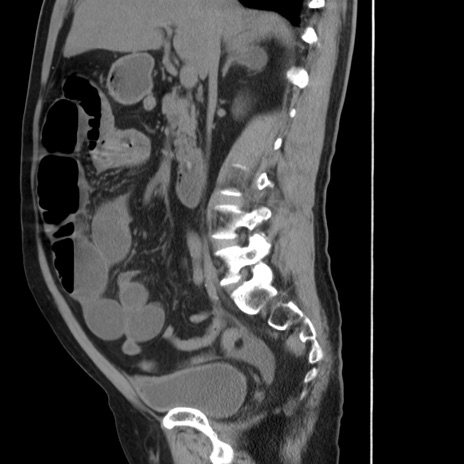

症例20(矢状断像)

【症例】 60歳代男性

【主訴】 腹部膨満、嘔吐

【現病歴】5日前頃より倦怠感を認め食事量減少し4日前の朝嘔吐、食事摂取困難となった。 3日前近医受診し点滴施行され整腸剤などを処方された。 当日他院を受診し、腹部膨満著明、炎症反応の上昇(CRP10.8、WBC11200)あり、紹介受診となる。

【身体所見】 意識JCS1 受け答えがはっきりしないBP 111/57mHg、 P 67bpm、、BT35.2°C、SpO2 97%(RA)、 腹部:膨隆、打診で鼓音あり、全体的に圧痛有り、腸蠕動音(-)、反跳痛ははっきりせず。

【データ】WBC 11400、CRP 14.20